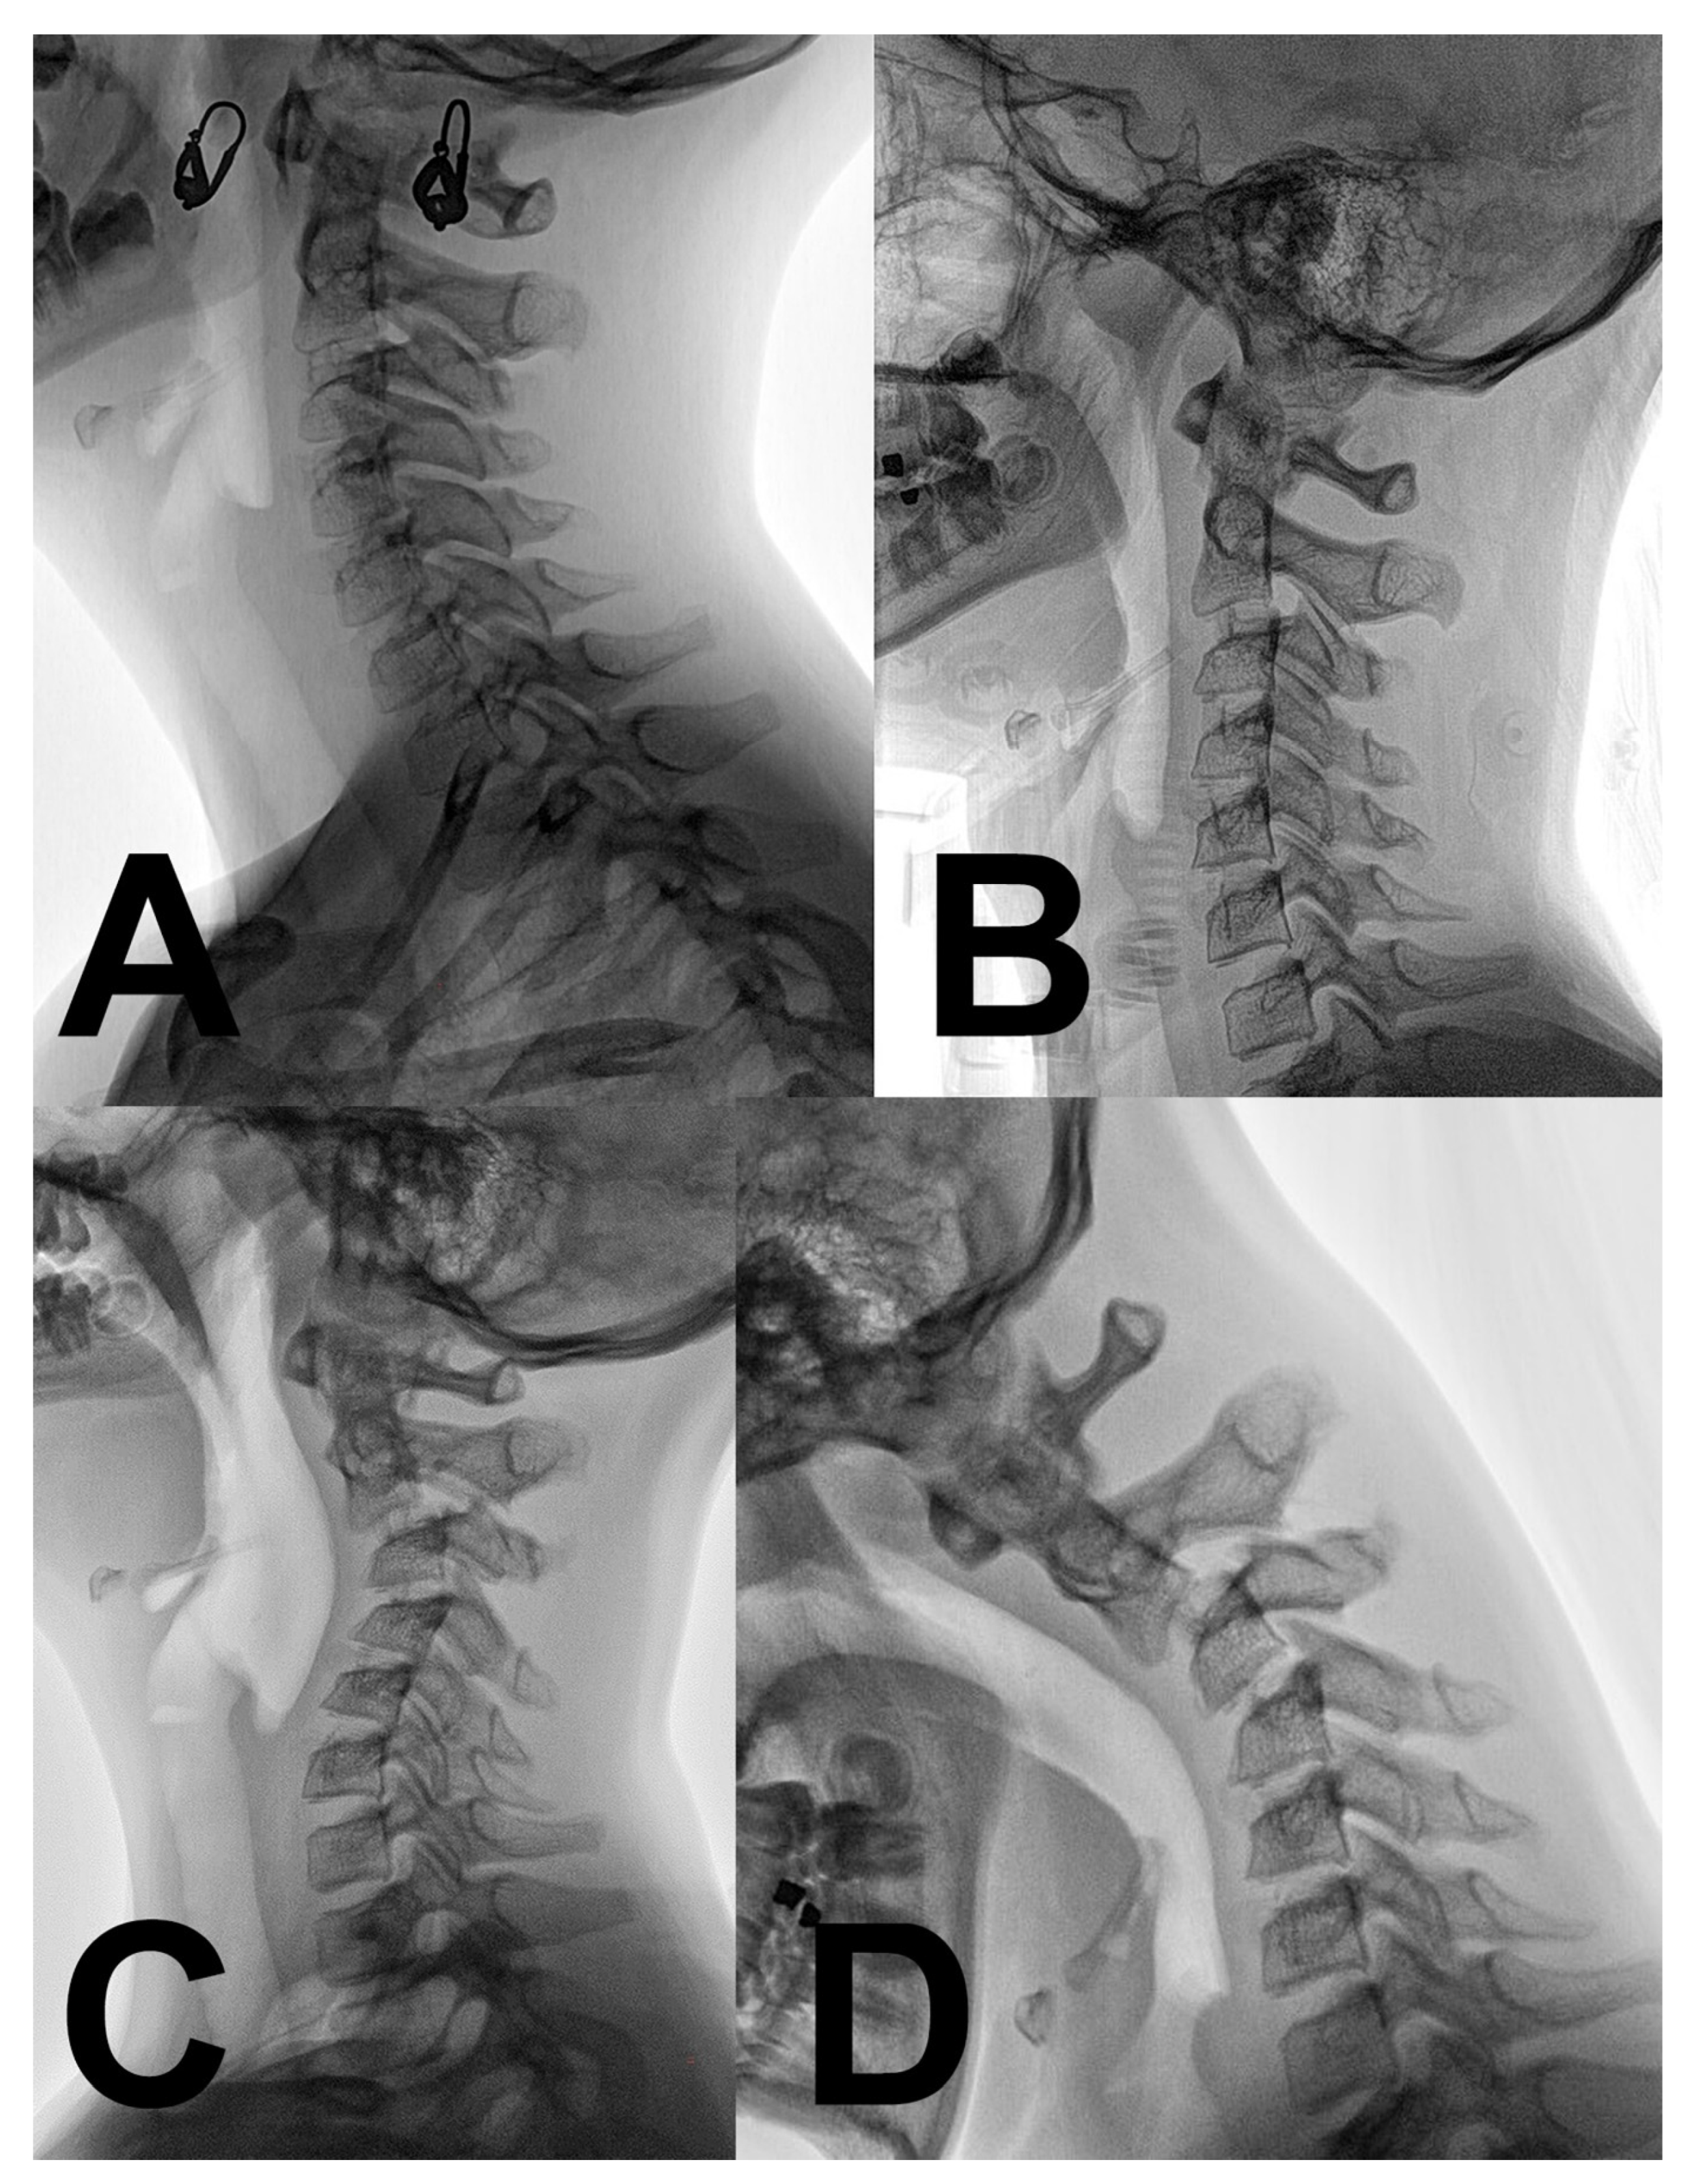

2. Case Report